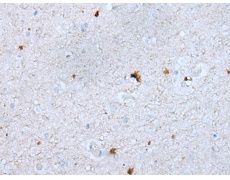

IHC positive control: |

Human brain |